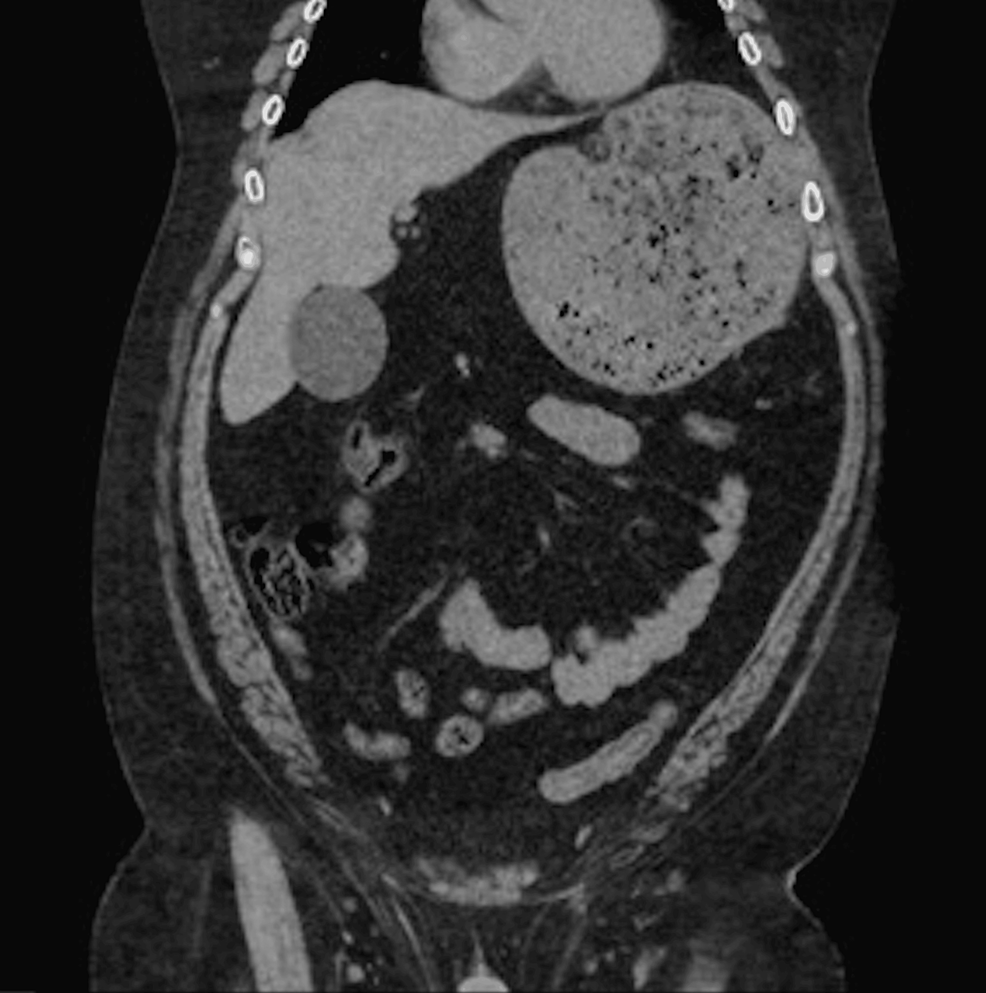

From radiopaedia.org

Gastric volvulus with perforation Image Endoscopic Decompression Of Gastric Volvulus Endoscopic decompression was trialled initially in 81 patients and successful in 20 (26.3%) patients. The purpose of this document from the american society for gastrointestinal endoscopy’s standards of practice committee is to provide. First, we recommend early endoscopy and decompression to identify the. Treatment is initiated with gastric decompression via a nasogastric tube or endoscopic decompression. The management of gastric. Endoscopic Decompression Of Gastric Volvulus.